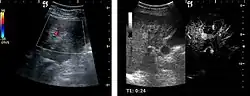

HCC appearance on 2D ultrasound is that of a solid tumor, with imprecise delineation, with heterogeneous structure, uni- or multilocular (encephaloid form). An "infiltrative" type is also described which is difficult to discriminate from liver nodular reconstruction in cirrhosis. Typically HCC invades liver vessels, primarily the portal veins but also the hepatic veins . Doppler examination detects a high speed arterial flow and low impedance index (correlated with described changes in tumor angiogenesis). The spatial distribution of the vessels is irregular, disordered. CEUS examination shows hyperenhancement of the lesion during the arterial phase. During the portal venous phase there is a specific "wash out" of ultrasound contrast agent (UCA) and the tumor appears hypoechoic during the late phase. Poorly differentiated tumors may have a stronger wash out leading to an isoechoic appearance to the liver parenchyma during portal venous phase. This appearance was found in approx. 30% of cases. The described changes have diagnostic value in liver nodules larger than 2 cm.

US examination is required to detect liver metastases in patients with oncologic history. In addition, the method can incidentally detect metastases in asymptomatic patients. Early identification (small sizes, small number) is important to establish an optimal course of treatment which can be complex (chemotherapy, radiofrequency ablation, surgical resection) but welcomed. In addition, discrimination of synchronous lesions that have a different nature is also important knowing that up to 25–50% of liver lesions less than 2 cm detected in cancer patients may be benign . US sensitivity for metastases detection varies depending on the examiner's experience and the equipment used and ranges between 40 and 80% . Sensitivity is conditioned by the size and acoustic impedance of the nodules. For a lesion diameter below 10 mm US accuracy is greatly reduced, reaching approx. 20%. Other elements contributing to lower US performance are: excessive obesity, fatty liver disease, hypomobility of the diaphragm, and certain patterns of hyperechoic or isoechoic metastases that can be overlooked or can mimic benign conditions. Conventional US appearance of metastases is uncharacteristic, consisting of circumscribed lesions, with clear, imprecise or "halo" delineation, with homogeneous or heterogeneous echo pattern. They can be single (often liver metastases from colonic neoplasm) or multiple. Echogenity is variable. When increased, they can compress the bile ducts (which may be dilated) and the liver vessels. Liver involvement can be segmental, lobar or generalized. In this situation a pronounced hepatomegaly occurs. Generally, metastases have non-characteristic Doppler vascular pattern, with few exceptions (carcinoid metastases). Cyst-adenocarcinoma metastases due to semifluid content may have a transonic appearance. When increasing, they can result in central necrosis. CEUS examination is a real breakthrough for detection and characterization of liver metastases.

Increased performance is based on identifying specific vascular patterns during the arterial phase and seeing metastases in contrast to normal liver parenchyma during the sinusoidal phase. CEUS increased accuracy is due to the different behavior of normal liver parenchyma (captures CA in Kuppfer cells) against tumor parenchyma (does not contain Kuppfer cells, therefore CEUS appearance is hypoechoic). To this adds the particularities of intratumoral circulation represented by a reduced arterial bed compared to that of the surrounding normal liver and the absence of the portal vessels . In terms of vascularity, metastases can be hypovascular (in gastric, colonic, pancreatic or ovarian adenocarcinomas) with hypoechoic pattern during arterial phase, and similar during portal venous and late phases, respectively hypervascular (neuroendocrine tumors, malignant melanoma, sarcomas, renal, breast or thyroid tumors) with hyperechoic appearance during arterial phase, with washout during the portal venous phase and hypoechoic pattern 30 seconds after injection.